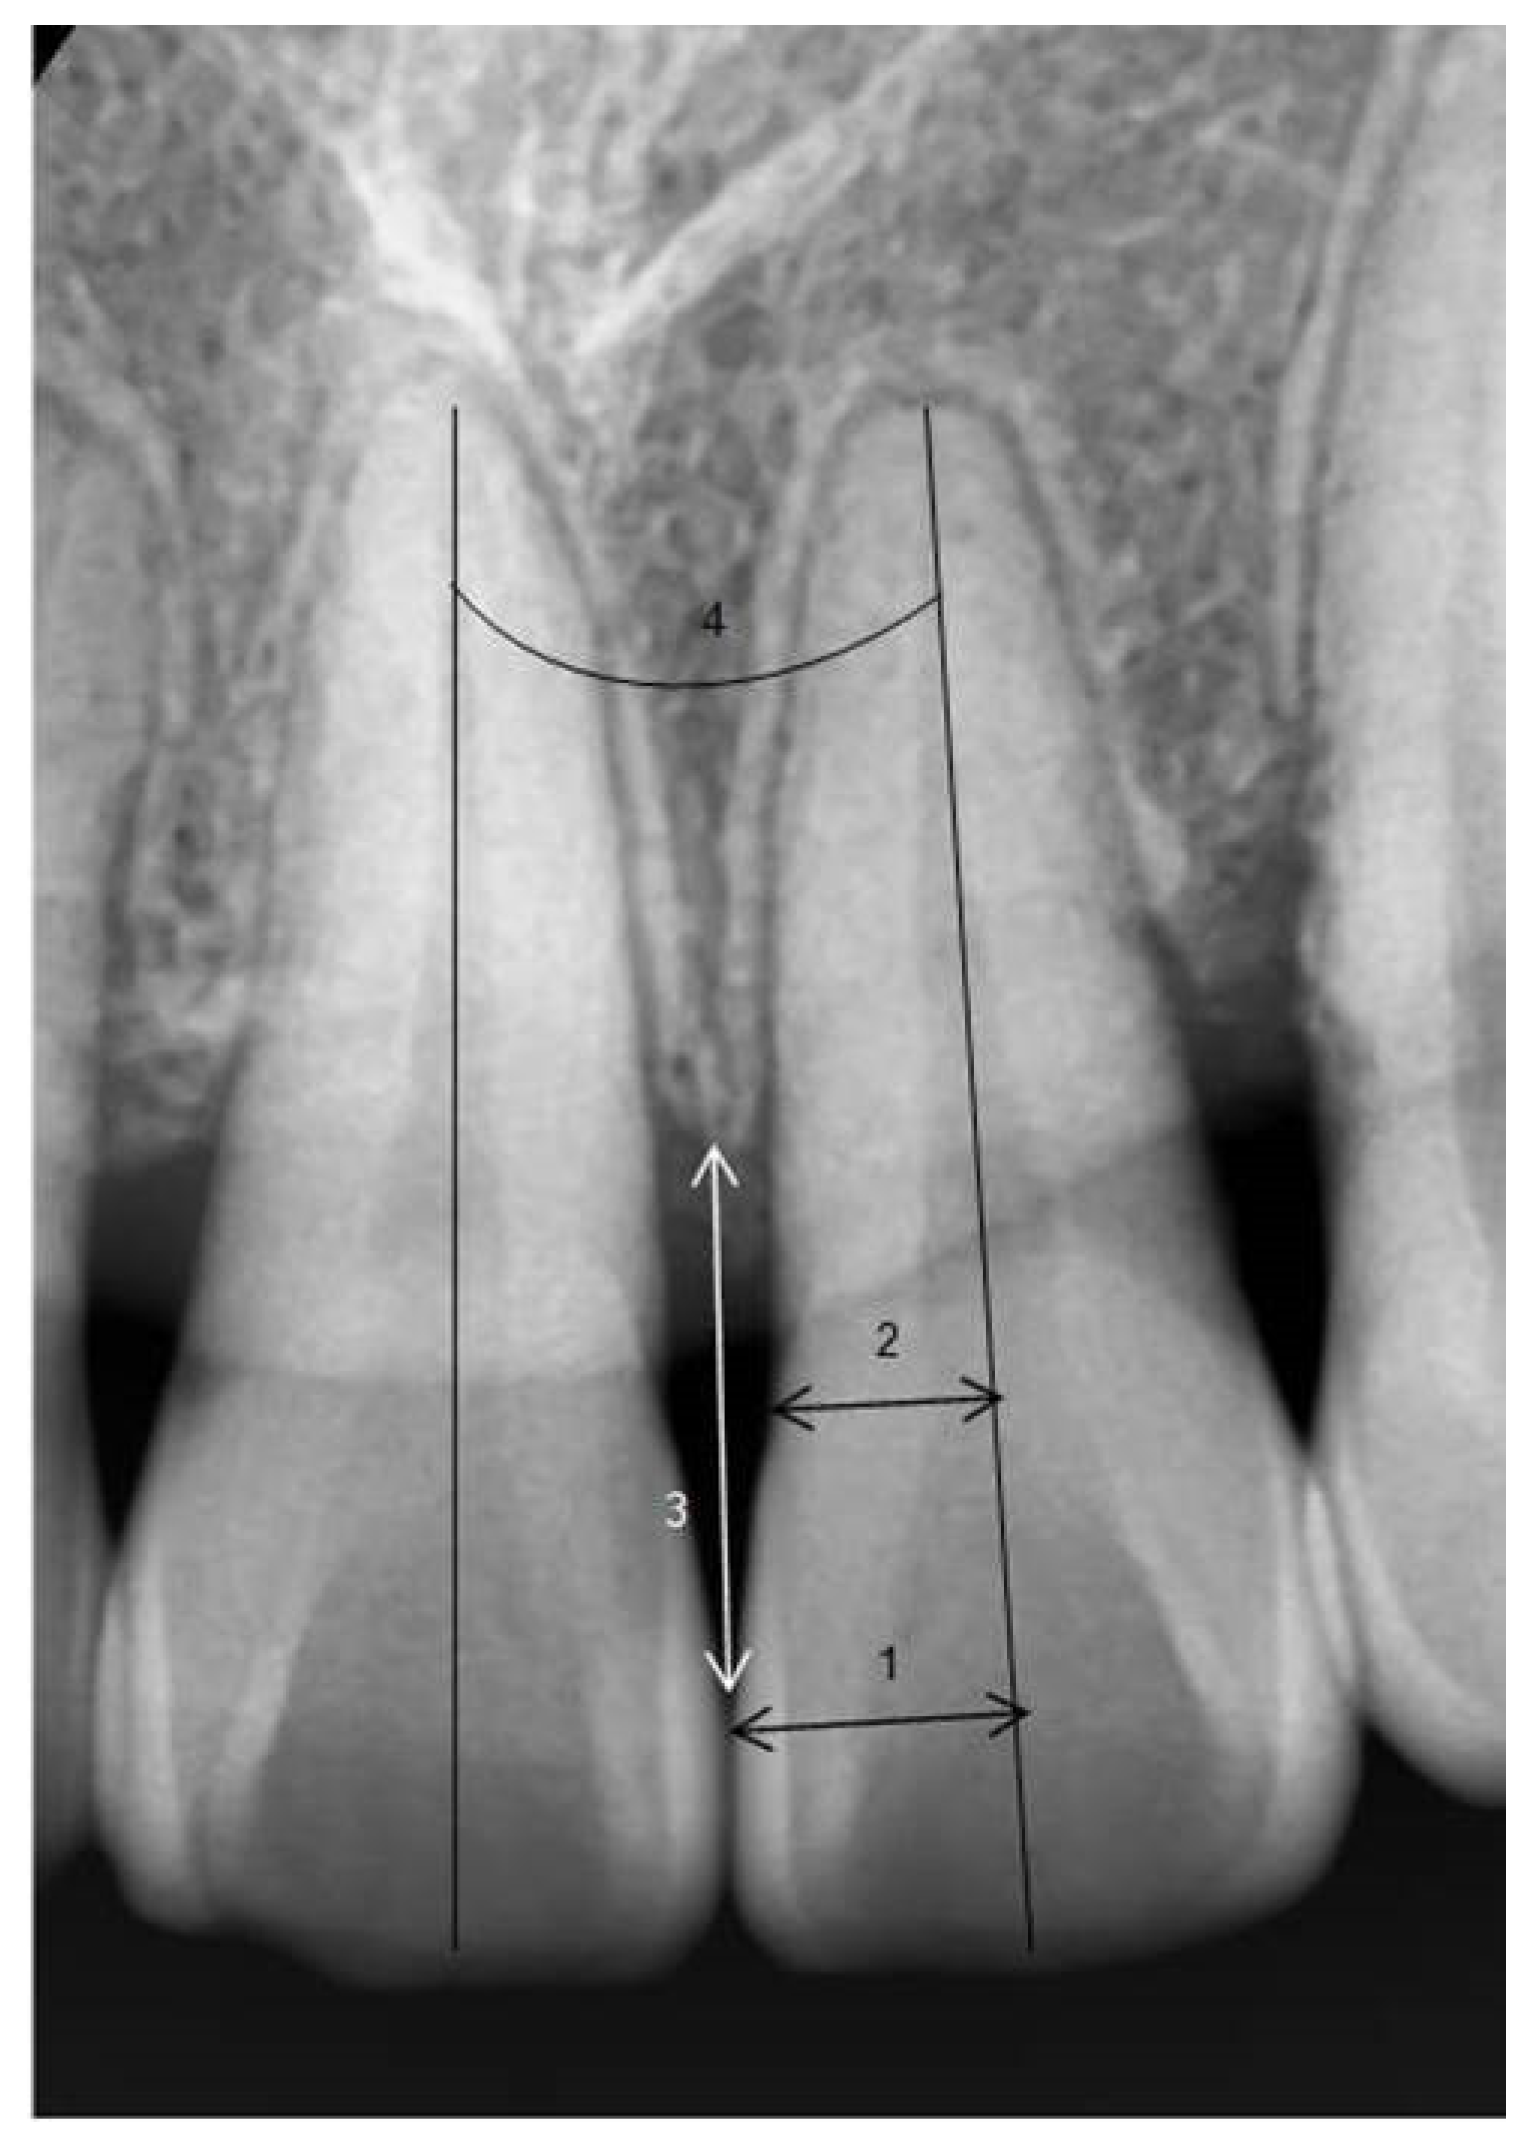

In periapical radiographs taken before orthodontic treatment, the long axis of the maxillary and mandibular central incisors was established. The ratio of the perpendicular distance from the long axis to the mesial contact point of the crown (1) to the perpendicular distance from the long axis to the mesial CEJ (cemento–enamel junction) (2) was calculated (crown ratio = (1)/(2)) [27].

To minimize errors due to magnification or distortion in periapical radiographs, the clinical average crown lengths of the central incisors were used as reference values, and the amount of alveolar bone height change (ΔTA = TA2 − TA1) was measured [28]. The distance from the contact point (or the most cervical point of the contact surface) of the maxillary and mandibular central incisors to the alveolar crest was measured, keeping the measurement parallel to the long axis of the left central incisor, and the difference in distance before and after orthodontic treatment was compared. If there was a space between the teeth without a contact point, the distance from the narrowest point between the mesial surfaces of both crowns and the alveolar crest was measured. The angle between the roots of the left and right maxillary and mandibular central incisors was measured in patients after completing orthodontic treatment (Figure 3).

Figure 3. Periapical radiographic measurements. 1, perpendicular distance from the mesial interproximal contact to the tooth long axis; 2, perpendicular distance from the mesial CEJ to the tooth long axis; 3, distance of alveolar bone–interproximal contact; 4, post-treatment root angulation classification of black triangle according to Jemt Index.